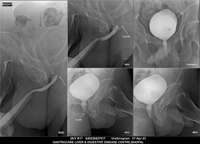

Section: URETHROGRAM Total: 95 images